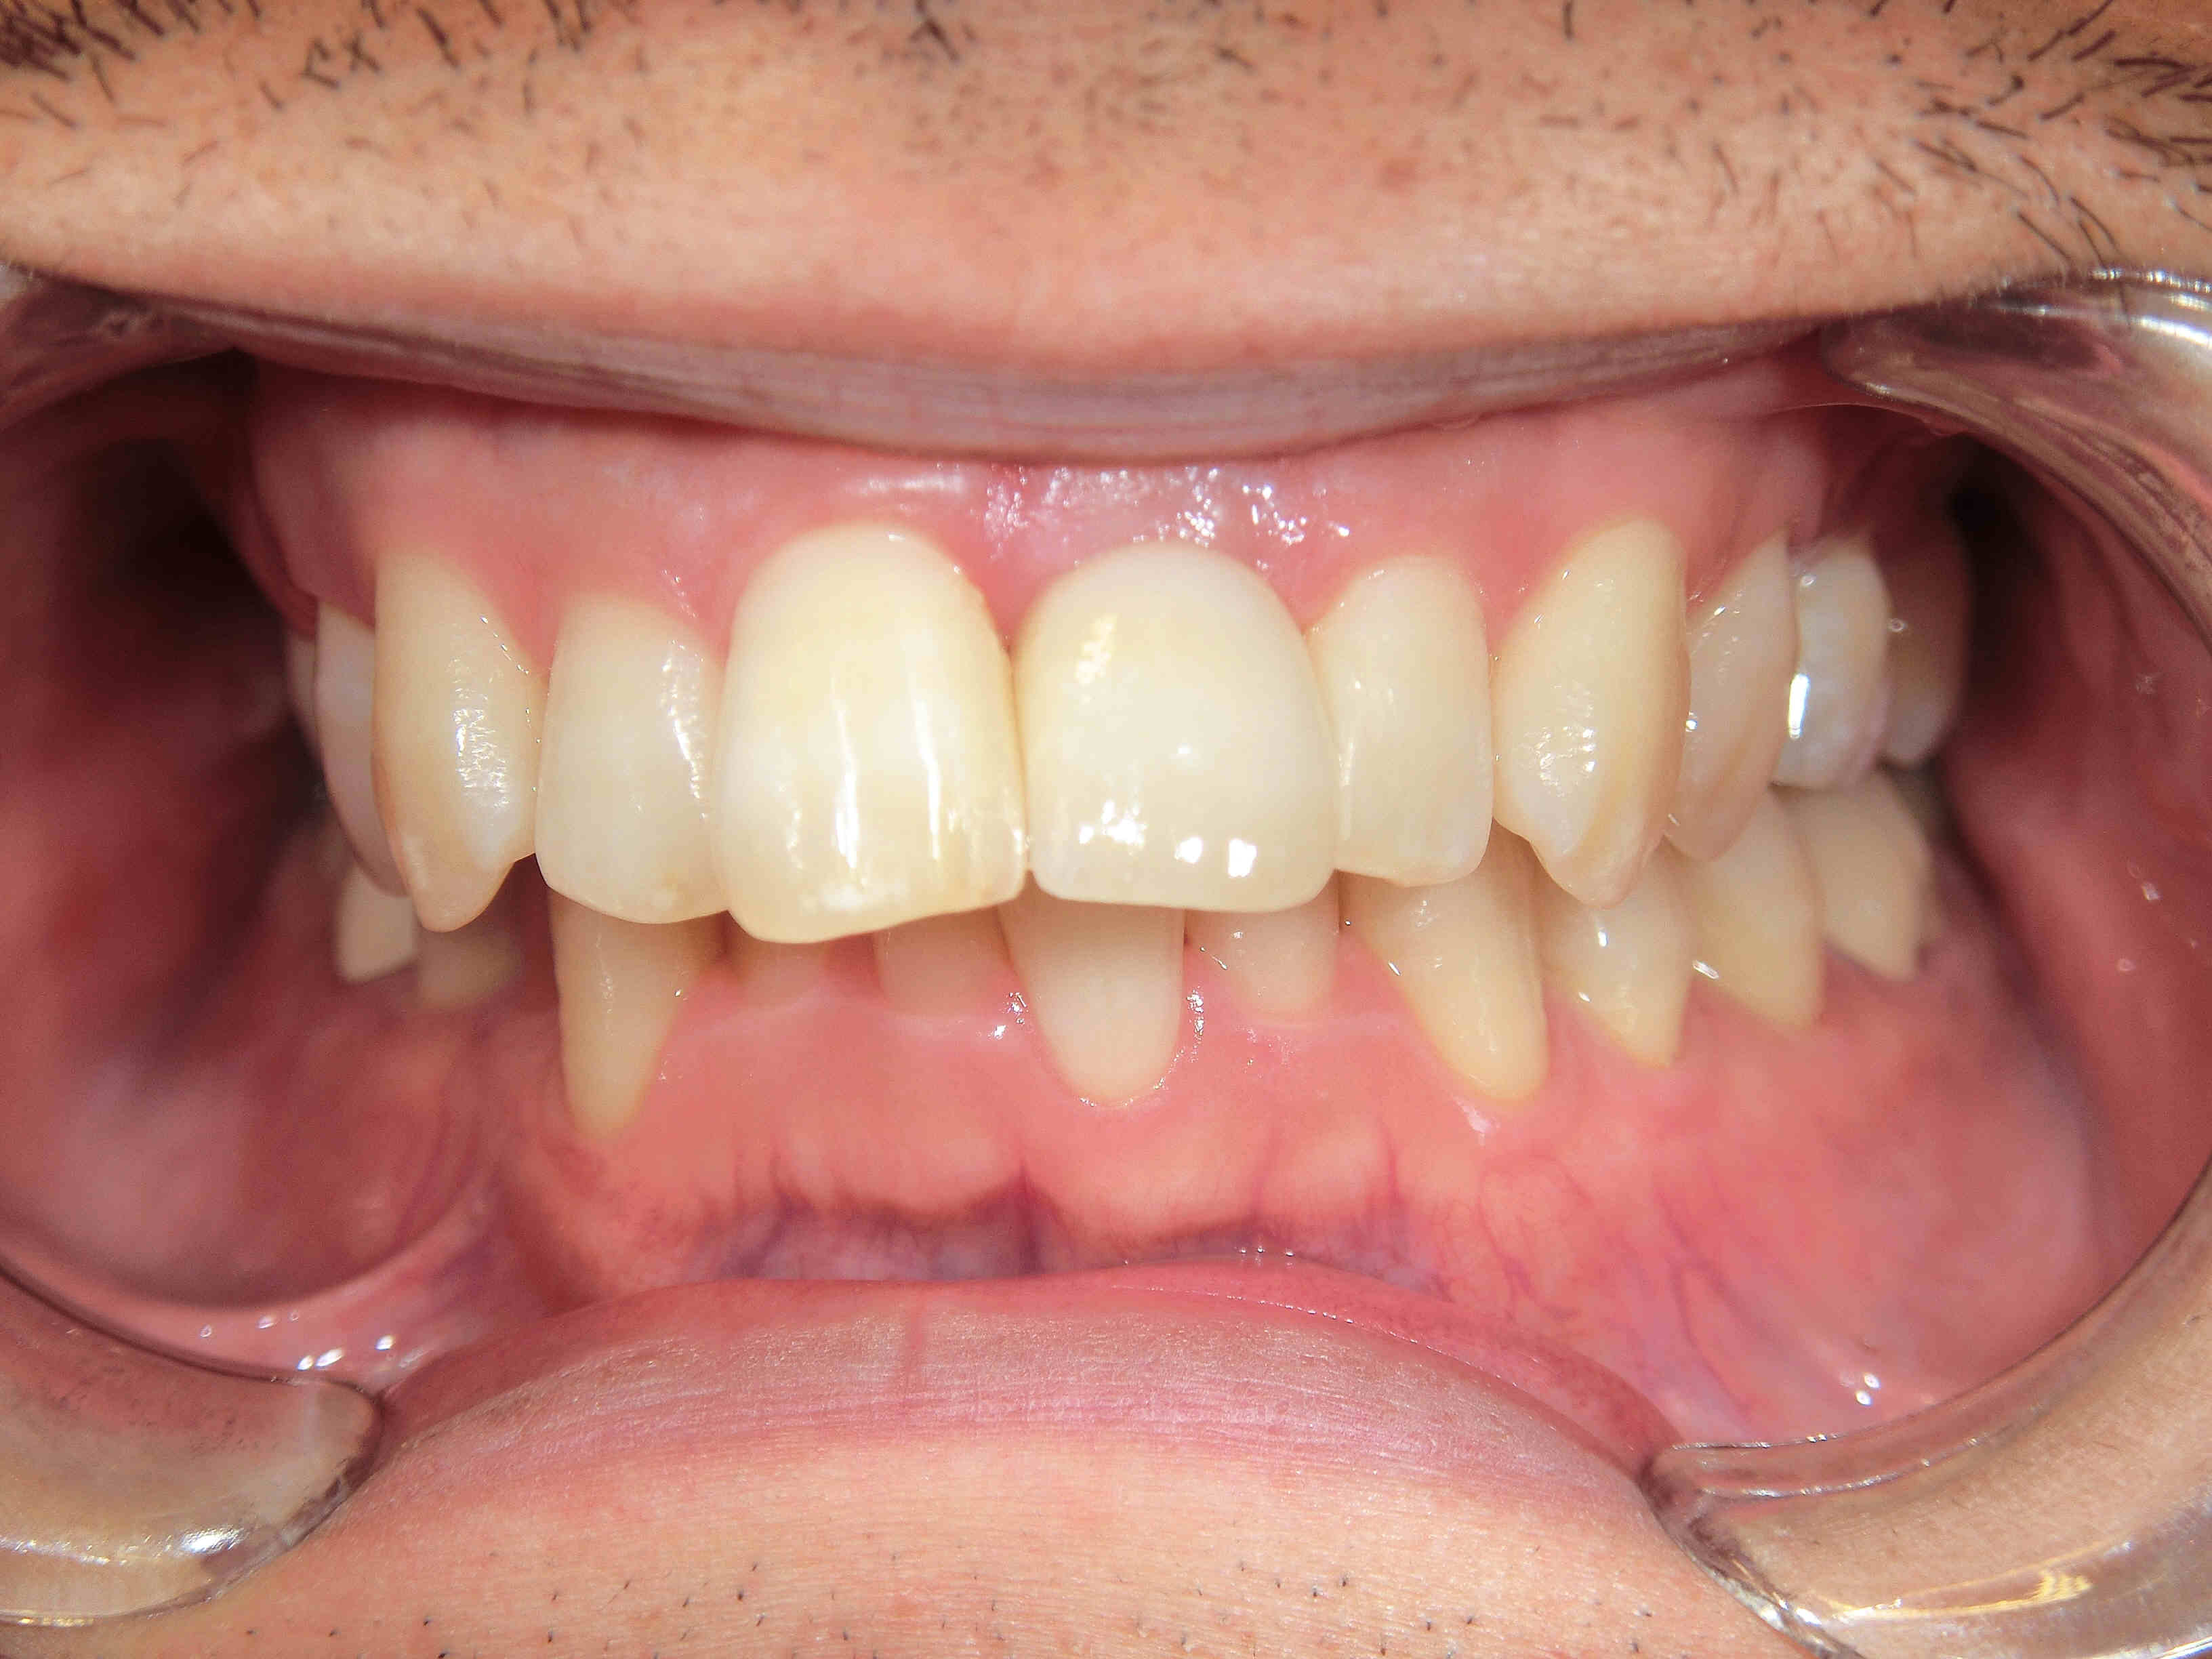

下の写真は、治療完了後の状態です。

歯を支えていた骨にも骨折が認められたため、骨を補填する処置(GBR=骨誘導再生法)を行ったうえで、インプラントの埋入を行いました。

治療後には、見た目や機能面で自然に近い仕上がりを実現できたことから、患者様にもご満足いただけた様子でした。